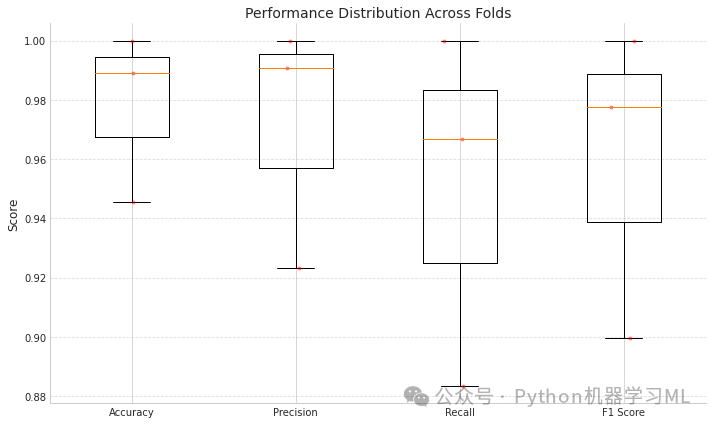

第一阶段:交叉验证性能评估

这部分代码实现了分层K折交叉验证,用于全面评估模型性能并展示结果分布。

python# 导入分层k折交叉验证和性能评估所需的库

from sklearn.model_selection import StratifiedKFold # 导入分层K折交叉验证

from sklearn.metrics import accuracy_score, precision_score, recall_score, f1_score # 导入评估指标函数

defcross_validate_model_performance(model, X, y, n_splits=5):

"""

使用分层k折交叉验证评估模型性能

参数:

model: 待评估的机器学习模型

X: 特征数据

y: 标签数据

n_splits: 交叉验证折数,默认为5

返回:

包含各项性能指标的字典

"""

# 初始化分层k折交叉验证

skf = StratifiedKFold(n_splits=n_splits, shuffle=True, random_state=42) # 创建分层k折交叉验证对象,设置折数、打乱数据和随机种子

# 指标存储列表

accuracies = [] # 用于存储每折的准确率

precisions = [] # 用于存储每折的精确率

recalls = [] # 用于存储每折的召回率

f1_scores = [] # 用于存储每折的F1分数

print(f"\n=== {n_splits}-Fold Cross-Validation Performance ===") # 打印交叉验证标题

# 执行交叉验证

for fold, (train_idx, test_idx) inenumerate(skf.split(X, y)): # 遍历每一折的训练和测试索引

print(f"\nFold {fold+1}/{n_splits}") # 打印当前折数

# 拆分数据

X_train_fold, X_test_fold = X[train_idx], X[test_idx] # 根据索引获取训练特征和测试特征

y_train_fold, y_test_fold = y[train_idx], y[test_idx] # 根据索引获取训练标签和测试标签

# 在当前折上训练模型

model.fit(X_train_fold, y_train_fold, epochs=3, batch_size=16, verbose=0) # 训练模型,设置训练轮数、批量大小和不显示进度

# 在测试折上评估模型

y_pred_fold = model.predict(X_test_fold) # 预测结果(概率)

y_pred_classes = np.argmax(y_pred_fold, axis=1) # 将概率转换为类别索引

# 计算评估指标

acc = accuracy_score(y_test_fold, y_pred_classes) # 计算准确率

prec = precision_score(y_test_fold, y_pred_classes, average='macro') # 计算宏平均精确率

rec = recall_score(y_test_fold, y_pred_classes, average='macro') # 计算宏平均召回率

f1 = f1_score(y_test_fold, y_pred_classes, average='macro') # 计算宏平均F1分数

# 存储评估指标

accuracies.append(acc) # 添加准确率到列表

precisions.append(prec) # 添加精确率到列表

recalls.append(rec) # 添加召回率到列表

f1_scores.append(f1) # 添加F1分数到列表

# 打印当前折的结果

print(f" Accuracy: {acc:.4f}") # 打印准确率

print(f" Precision: {prec:.4f}") # 打印精确率

print(f" Recall: {rec:.4f}") # 打印召回率

print(f" F1 Score: {f1:.4f}") # 打印F1分数

# 计算并打印所有折的平均性能

print("\nAverage performance across all folds:") # 打印平均性能标题

print(f" Accuracy: {np.mean(accuracies):.4f} ± {np.std(accuracies):.4f}") # 打印平均准确率及标准差

print(f" Precision: {np.mean(precisions):.4f} ± {np.std(precisions):.4f}") # 打印平均精确率及标准差

print(f" Recall: {np.mean(recalls):.4f} ± {np.std(recalls):.4f}") # 打印平均召回率及标准差

print(f" F1 Score: {np.mean(f1_scores):.4f} ± {np.std(f1_scores):.4f}") # 打印平均F1分数及标准差

# 绘制性能分布图

metrics = { # 创建指标字典

'Accuracy': accuracies, # 准确率列表

'Precision': precisions, # 精确率列表

'Recall': recalls, # 召回率列表

'F1 Score': f1_scores # F1分数列表

}

plt.figure(figsize=(10, 6)) # 创建10x6大小的图形

# 创建箱线图

plt.boxplot([metrics[m] for m in metrics.keys()], labels=metrics.keys()) # 绘制所有指标的箱线图

plt.title('Performance Distribution Across Folds') # 设置图表标题

plt.ylabel('Score') # 设置y轴标签

plt.grid(axis='y', linestyle='--', alpha=0.7) # 添加网格线

# 添加单个点

for i, m inenumerate(metrics.keys()): # 遍历每个指标

x = np.random.normal(i+1, 0.04, size=len(metrics[m])) # 为点生成稍微偏移的x坐标,增加可视性

plt.plot(x, metrics[m], 'r.', alpha=0.4) # 绘制点

plt.tight_layout() # 调整布局

plt.show() # 显示图形

return metrics # 返回指标字典

# 取消注释以运行交叉验证(注意:这可能很耗时)

cross_val_metrics = cross_validate_model_performance(model3, X_valid, y_valid, n_splits=3) # 使用3折交叉验证评估模型

=== 3-Fold Cross-Validation Performance ===

Fold 1/3 Accuracy: 0.9457 Precision: 0.9232 Recall: 0.8834 F1 Score: 0.8995

Fold 2/3 Accuracy: 0.9891 Precision: 0.9907 Recall: 0.9667 F1 Score: 0.9778

Fold 3/3 Accuracy: 1.0000 Precision: 1.0000 Recall: 1.0000 F1 Score: 1.0000

Average performance across all folds: Accuracy: 0.9783 ± 0.0235 Precision: 0.9713 ± 0.0342 Recall: 0.9500 ± 0.0490 F1 Score: 0.9591 ± 0.0431

这段代码提供了一套全面的深度学习模型评估工具,分为三个主要阶段:

交叉验证性能评估:

-

- 使用分层K折交叉验证方法评估模型在不同数据划分上的性能稳定性

- 计算准确率、精确率、召回率和F1分数等标准评估指标

- 通过箱线图直观展示模型性能分布,帮助评估性能波动情况